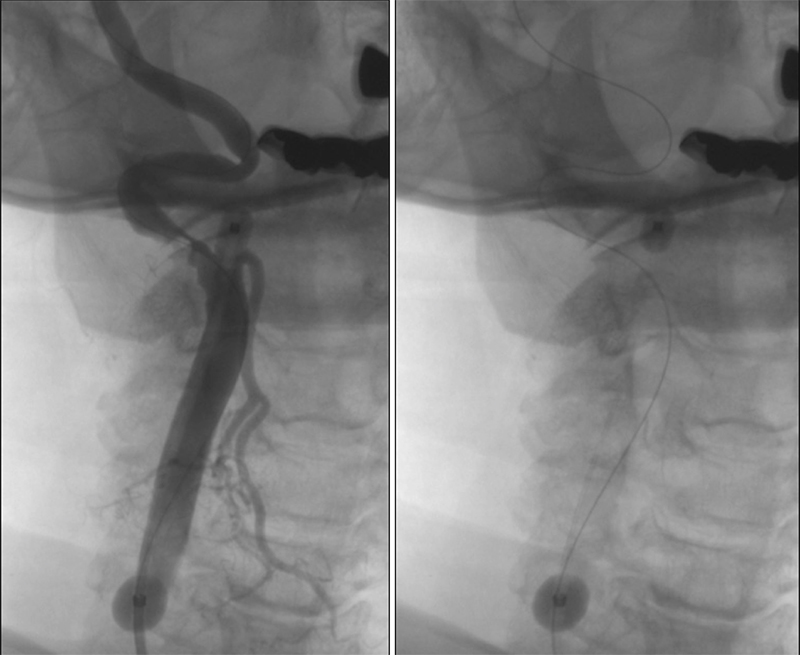

Εικόνα 1: Πλάγια και λοξή λήψη εγχύσεως στην δεξιά κοινή καρωτίδα. Έκκεντρη και ανώμαλη αθηρωματική πλάκα του οπισθίου τοιχώματος του δεξιού καρωτιδικού βολβού και της εκφύσεως της έσω καρωτίδος χωρίς εξέλκωση με στένωση 80%. Η μεταβολβική ελίκωση, καθιστά την τοποθέτηση φίλτρου προστασίας επικίνδυνη λόγω ελλείψεως χώρου προσγείωσης του φίλτρου (landing zone).

Εικόνα 2: Χρησιμοποίηση εγγύς συστήματος προστασίας τύπου MOMA με διάταση των μπαλονιών στην έξω και στην κοινή καρωτίδα.